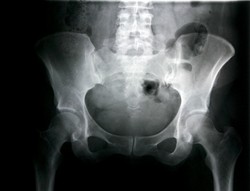

Kabar mengejutkan sekaligus memukul datang dari buah hati kedua yang telah dinanti-nanti pasangan Jeff dan Jordan Wonsmos. Menurut dokter, ada satu organ si bayi yang tumbuh di luar tubuhnya. Mereka khawatir si bayi takkan pernah merasakan hidup normal.